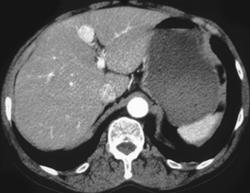

Superior Mesenteric Vein (SMV) Aneurysm